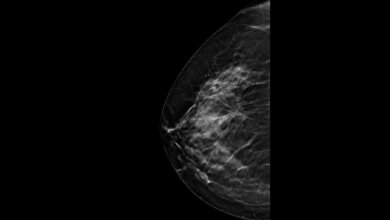

Der Hintergrund: Die Weiterentwicklung zur DBT stellt eine Technologie zur Verfügung, die durch die Berechnung eines Pseudo-3D-Datensatzes Überlagerungseffekte durch Gewebe reduziert und somit diagnostische Vorteile zeigt. Gleichzeitig erlaubt die Kombination mit sogenannten synthetischen Mammogrammen, die mit Computerunterstützung aus den Tomosynthese-Datensätzen berechnet werden, einen Vergleich mit Voraufnahmen und eine visuelle Einschätzung der Brustdichte.

Die aktuelle ToSyMa-Subanalyse konzentrierte sich auf die Brustkrebsdiagnostik in den vier Brustdichtekategorien. Das Ergebnis: Die Detektionsrate von invasiven Brustkrebs-Diagnosen mittels Tomosynthese unter den Studienteilnehmerinnen, die ein extrem dichtes Brustdrüsengewebe haben, war um etwa 250 Prozent höher als bei der Standardmethode der digitalen Mammographie. „Das legt nahe, dass ein Mammographie-Screening mit digitaler Brust-Tomosynthese radiologische Summationseffekte und Überlagerungseffekte deutlich mindert und den Grenzen der digitalen Mammographie entgegenwirkt“, so Studienmanagerin Prof. Dr. Stefanie Weigel.